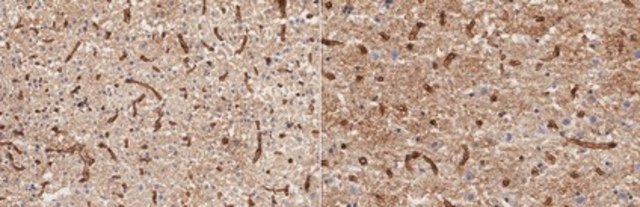

Evaluated by Immunohistochemistry in rat brain frozen tissue sections.

Immunohistochemistry Analysis: A 1:50 dilution of this antibody detected Aquaporin-4 in rat brain frozen tissue sections.